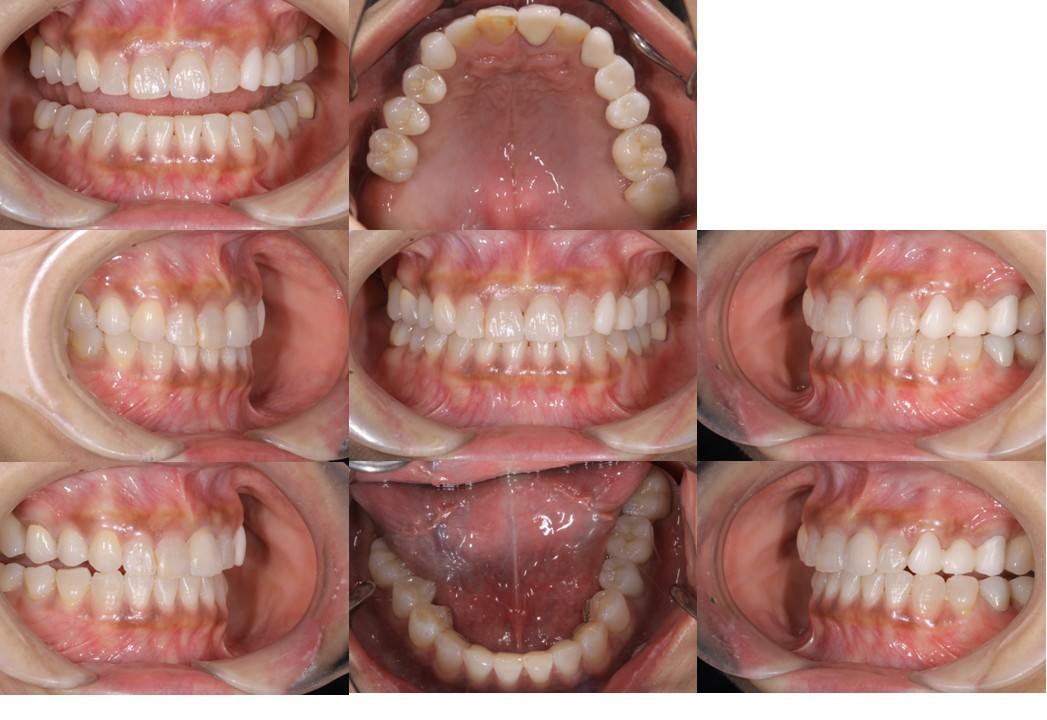

「生活歯髄保存療法」症例 ●初診時年齢30代 女性

機能的な咀嚼障害を主訴に来院(図18・19)。咬合状態は不安定で、矯正治療を含めた全顎的な治療が必要と診断した。治療計画では右上4・6、左上4・6、左下6部に、それぞれインプラント治療を計画した。右上5、左上5は、隣在歯が近遠ともインプラント治療になるため感覚受容器が乏しくなることが予測されるため、歯髄の有無が大きく影響されやすい環境と判断した。

(図18)初診時の口腔内写真

前歯部には叢生が存在しアンテリアガイダンスが失われた状態

上顎の臼歯の咬合面形態が大きく崩壊し、バーティカルストップを失ったことによる咬合の不安定が予測される